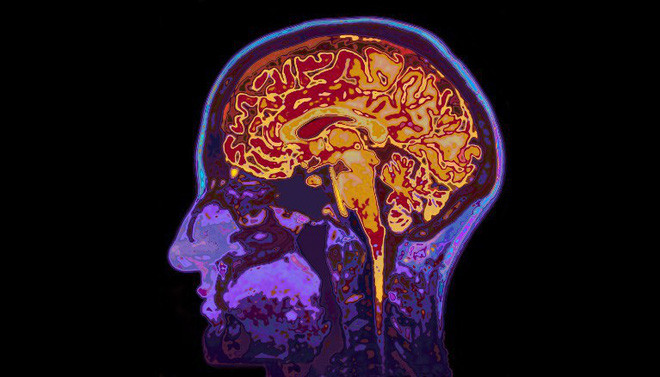

Não bộ người phụ nữ bí ẩn hơn ta tưởng nhiều.

Nhưng khi nghiên cứu não bộ người phụ nữ, nghiên cứu này bắt đầu đi theo một chiều hướng hoàn toàn khác: Hóa ra não bộ người phụ nữ bí ẩn hơn ta tưởng nhiều. Ta vẫn biết phụ nữ khó hiểu, nhưng hóa ra mọi thứ không chỉ dừng lại tại đó.

Các nhà khoa học tìm ra rằng não bộ người phụ nữ thường xuất hiện hiện tượng “vi chimera nam giới – male microchimerism”, về cơ bản, thì là có sự xuất hiện của ADN nam giới đến từ một cá nhân khác, có dấu hiệu gene khác biệt với toàn bộ các tế bào khác trong cơ thể người phụ nữ.

Theo nghiên cứu trên, thì có tới “63% phụ nữ được thử nghiệm (37 trên 59 người) có hiện tượng vi chimera nam giới trong não. Hiện tượng này xuất hiện ở nhiều phần của não bộ”.

Hiện tượng vi chimera nam giới xuất hiện ở nhiều phần của não bộ.